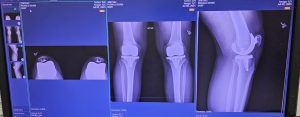

There comes a moment in every serious martial artist’s life when the body begins to speak more loudly than the ego. For some, it’s a minor injury. For others, like myself, it is something far more …